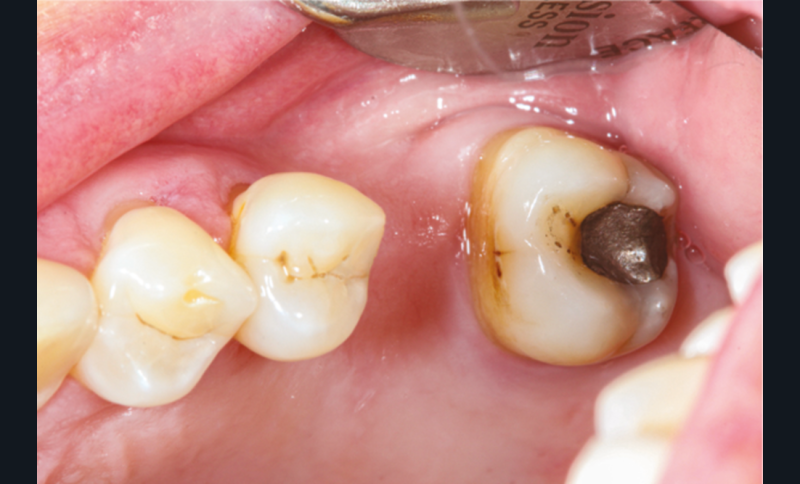

Cette version, quand elle se produit, modifie les espaces interdentaires et complique l’hygiène proximale des patients. Des caries peuvent alors se développer en interproximal sans que cela soit forcément visible à l’examen visuel (fig. 3 et 4). Les radios de type bite-wing (rétro-coronaires) prennent alors tout leur sens (fig. 5 et 6).

La répartition de la charge occlusale sur l’ensemble d’une arcade est aussi perturbée après une ou plusieurs extractions, ce qui peut occasionner des surcharges occlusales pour les dents restantes. Selon le délabrement coronaire de la dent [10], une fracture coronaire amélo-dentinaire ou corono-radiculaire peut intervenir sous cette surcharge occlusale et engager le pronostic de la dent concernée (fig. 14 à 17).